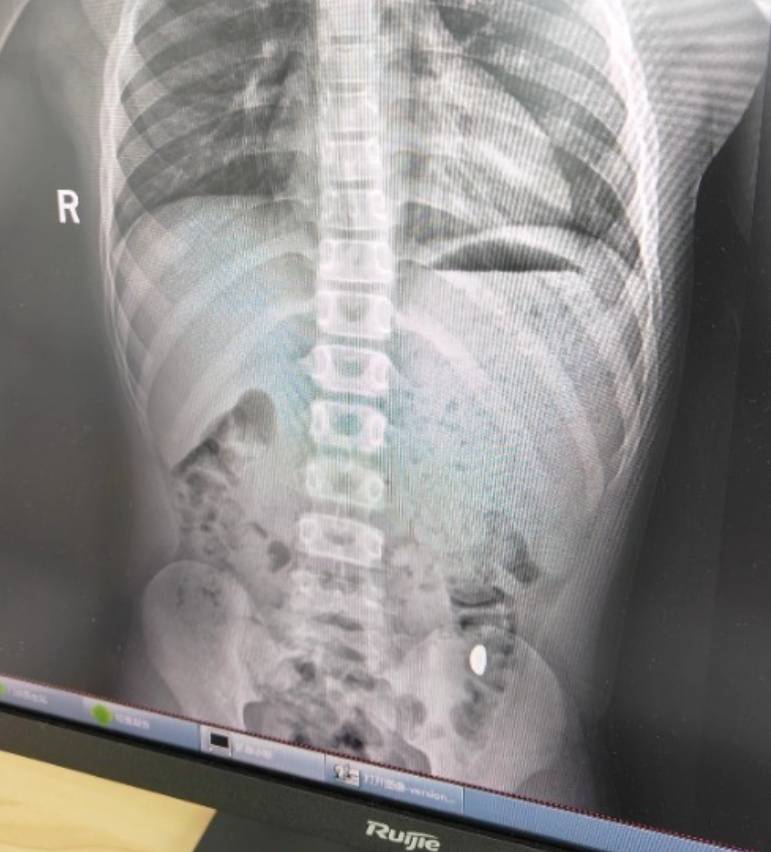

右下加亮点为金豆比特币目前价格。